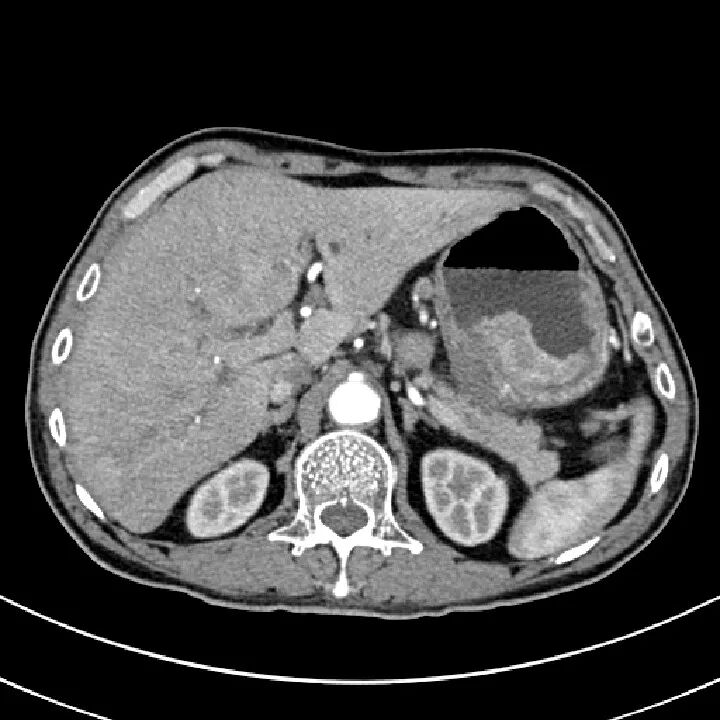

肾挫伤

肾挫伤是一种比较多见的肾损伤,肾组织损伤较轻,肾包膜和肾盂大多保持完整,肾实质内产生瘀血或血肿,并有少量血液流入肾盂导致血尿。肾挫伤在X线造影片上可不显示形态上的改变。一般均能自行愈合而不造成严重后果。